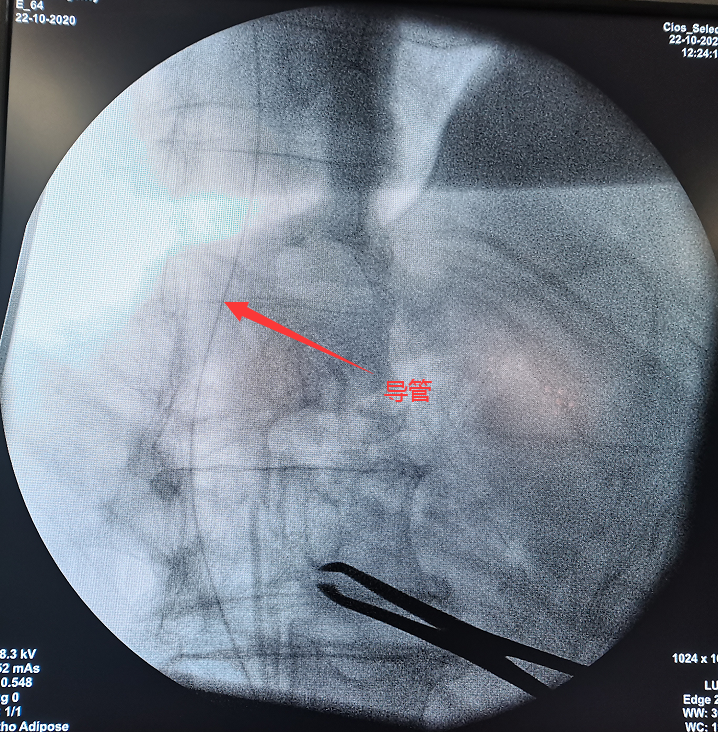

影像结果显示:电极有移位

输注泵

为输注泵注入药物(吗啡)

手术植入